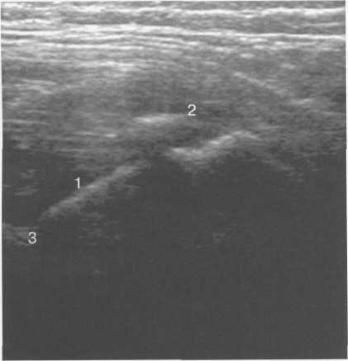

Рис. 19.83. Область хрящевого большого вертела (11 мес).

1 — контур шейки бедра; 2 — хрящевая зона области большого вертела; 3 — контур диафиза бедра.